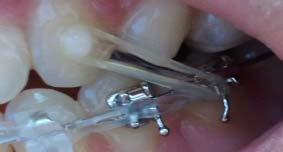

아!그리고 하악 밑에 달앗던 스크류 하나 뺐는데..정말..드라이버로 나사를 빼는..그런 기분이랄까

아프진 않았는데..기분이좀 이상했다는!!!